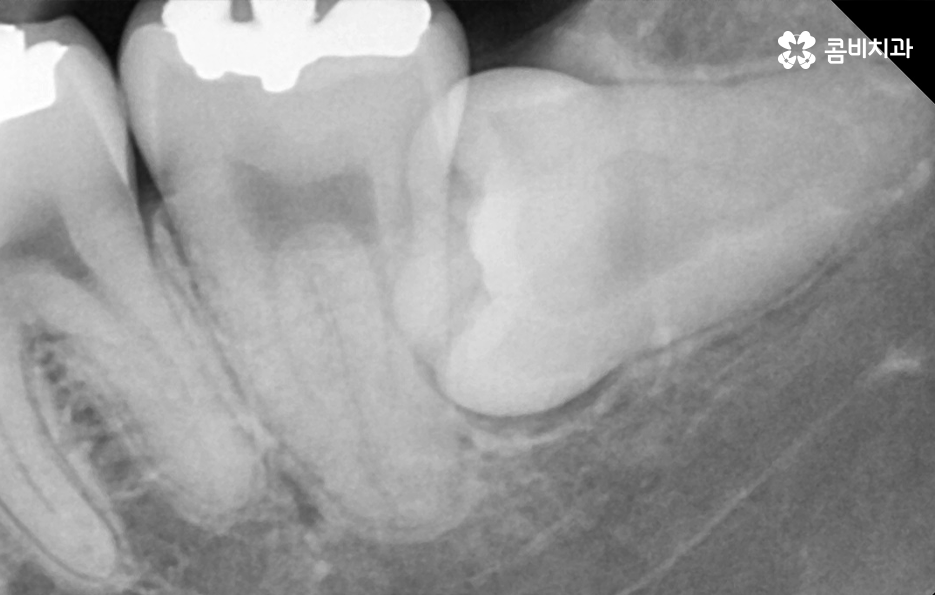

누운 사랑니로 인해 인접한 어금니에 충치가 발생하기 더 쉬운 이유는 위 사진처럼 발치 후 사진을 보더라도 치아의 구조상 치아의 하단 부분은 단단한 법랑질이 아닌 상아질로 이뤄져 있기 때문에 누운 사랑니로 인해 세균이 좀더 침투하기 쉬운 상태라는 점도 누워있는 사랑니를 발치해야 할 이유 중 하나라고 할 거예요

위 사례 이미지의 경우 그래도 다행인 점은 사랑니 발치 시점이 늦지 않아서 완전 누운 사랑니 임에도 큰 고생은 안했던 사례라고 본다면 아래 환자분의 사례는 이미 사랑니 뿐 아니라 어금니 까지 충치가 심해진 사례라고 할 수 있는데요

위 사례 이미지의 경우 사랑니가 누워 있는 정도는 덜하지만 사랑니 발치 시점이 늦어져서 사랑니와 인접 치아 모두 충치가 심해진 사례라고 할 수 있어요